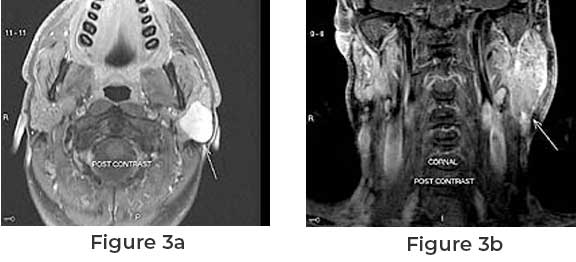

In cases where benign or malignant tumors affect the facial nerve, surgical intervention may involve cutting a portion of the nerve to remove the tumor safely. This procedure aims to eliminate or reduce the tumor’s impact while preserving as much nerve function as possible. Tumors like acoustic neuromas or facial nerve schwannomas often necessitate delicate surgical techniques to minimize nerve damage.